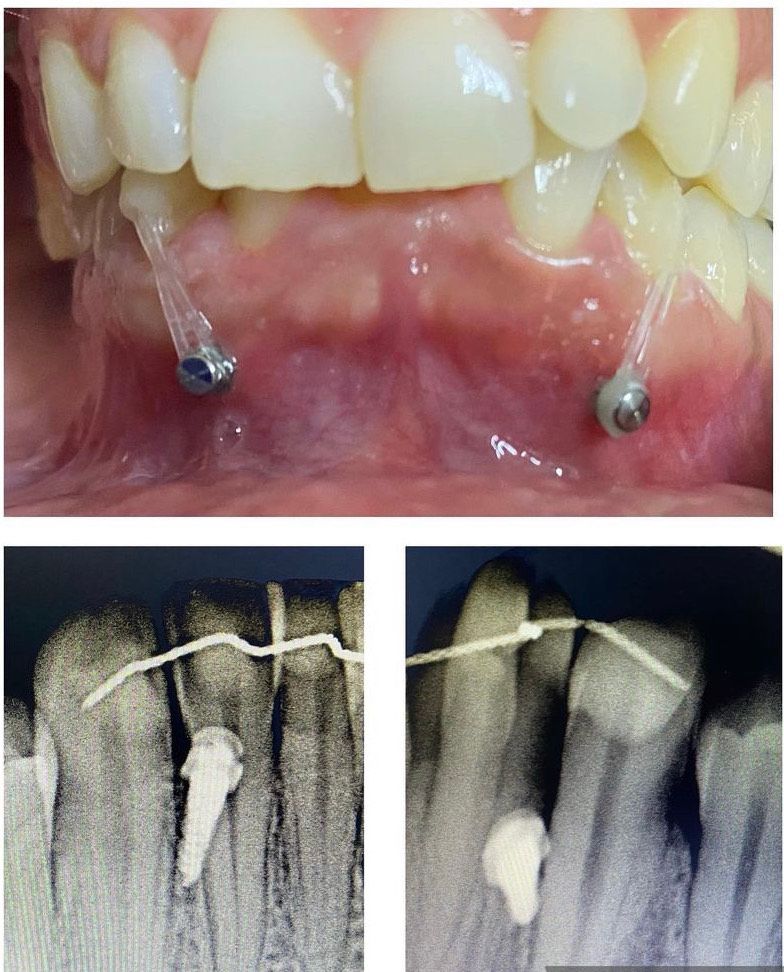

Laureata in Odontoiatria e Protesi dentaria nel 1998 a Napoli con 110 e lode. Master di II livello in Ortodonzia e Gnatologia, conseguiti all'Università Federico II di Napoli. Consulente ortodontico di studi a Napoli e provincia, decido di aprire anche un mio studio a Frattamaggiore, improntato all'Eccellenza Ortodontica. Tratto tutte le fasce d'età con tecniche ortodontiche innovative, impegnandomi a garantire standard di ortodonzia elevati e al di sopra della media. Esperta in ORTODONZIA INVISIBILE e nella gestione di casi complessi con canini inclusi, chiusura spazi estrattivi ed estrazioni di ottavi complicati. Mi occupo, inoltre, di cefalee e apnee notturne con dispositivi dedicati.